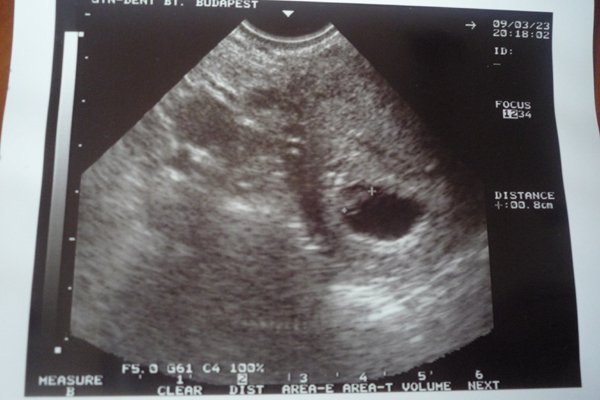

Jövő héten szerdán kell visszamennem UHU-ra, ha minden rendben lesz addig, márpedig miért ne lenne!